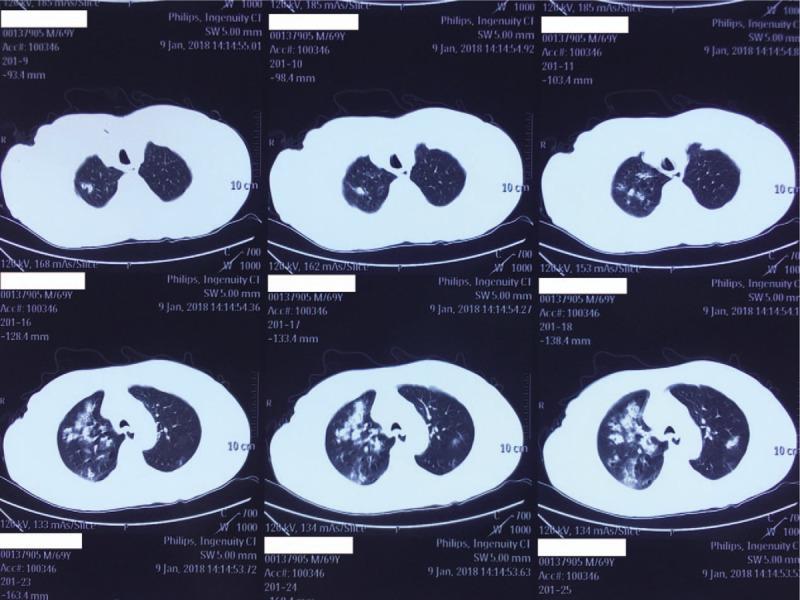

PATIENT CONCERNS

A 68-year-old male with no concerning medical history had developed a fever that reached 39.0°C, a productive cough that was sustained for 5 days, and hypodynamia. He was treated with azithromycin and alexipyretic in a nearby clinic for 2 days in which the symptoms were alleviated. However, 1 day later, the symptoms worsened, and he was taken to a local Chinese medicine hospital for traditional medicine treatment. However, his clinical condition deteriorated rapidly, and he then developed dyspnea and hemoptysis.

DIAGNOSIS

CA-MRSA pneumonia and septic shock. The sputum culture showed MRSA. Polymerase chain reaction of MRSA isolates was positive for PVL genes.